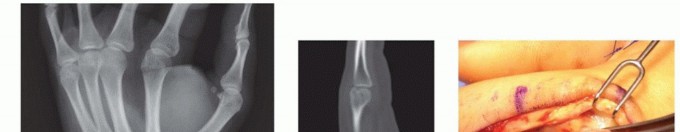

Clinical & Radiographic Imaging Archive